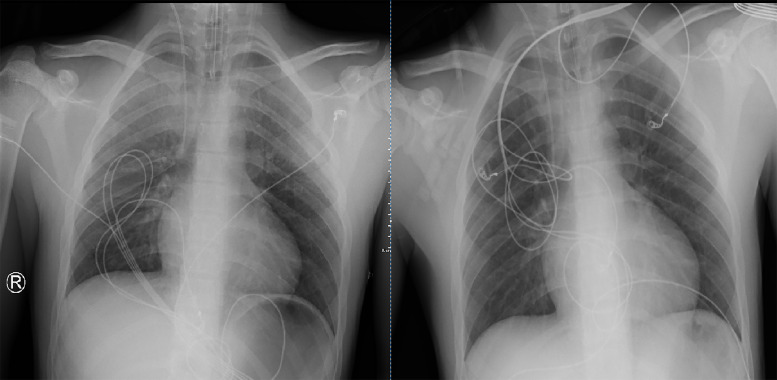

教学要点:神经源性肺水肿是脑外伤的一种罕见并发症,对于出现肺水肿的外伤患者,如果找不到其他原因,则应考虑神经源性肺水肿。

Teaching point: Neurogenic pulmonary edema is a rare complication of cerebral trauma and should be considered in trauma patients presenting with pulmonary edema when no other cause is found.